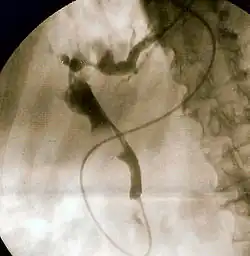

Il gold standard per la diagnosi di ostruzione biliare rimane ancora la colangio-pancreatografia endoscopica retrograda (ERCP). Questa tecnica implica l'uso di una sonda per endoscopia – che consiste in un tubo inserito nella bocca e che attraversa l'esofago, lo stomaco e quindi arriva al duodeno – per far giungere una piccola cannula nel dotto biliare; a quel punto, viene iniettato un mezzo di contrasto per opacizzare il condotto al fine di ottenere immagini a raggi X del sistema biliare. Su tali radiografie, note come colangiogrammi, i calcoli biliari sono visibili come aree non radiopache situate nel profilo del condotto. Per scopi esclusivamente diagnostici, l'ERCP è ora generalmente stata sostituita – per motivi legati alla sua invasività – dalla risonanza magnetica, mentre viene utilizzata di prima scelta per i pazienti critici in cui il ritardo nella diagnosi non è accettabile. Tuttavia, se l'indice di sospetto di colangite è alto, una ERCP è in genere eseguita per drenare il dotto biliare comune ostruito.[1]

La colangiopancreatografia endoscopica retrograda (ERCP) è l'approccio più comune per sbloccare il dotto biliare. Ciò comporta una procedura endoscopica (il passaggio di un tubo a fibre ottiche attraverso lo stomaco verso il duodeno), l'identificazione della papilla di Vater e quindi l'inserimento di un piccolo tubo nel dotto biliare. Viene in genere effettuata una sfinterotomia (ovvero una piccola incisione nello sfintere di Oddi) per facilitare il flusso della bile dal condotto e per consentire l'inserimento degli strumenti finalizzati all'estrazione dei calcoli che ostruiscono il dotto biliare comune; in alternativa, o in aggiunta, l'orifizio del dotto biliare comune può essere dilatato con un palloncino.[17] I calcoli possono essere rimossi mediante aspirazione diretta o tramite vari strumenti, compresi palloncini e cestelli per trainarli dal dotto biliare al duodeno. Affinché i calcoli più grandi siano rotti prima della rimozione, è possibile fare ricorso a un apparato noto come "litotritore meccanico" oppure a strumentazioni per litotrissia intracorporea laser o elettroidraulica.[18][19] I calcoli troppo grandi per essere rimossi o rotti meccanicamente tramite ERCP possono essere trattati mediante litotrissia extracorporea a onde d'urto: questa tecnica impiega onde d'urto acustiche prodotte al di fuori del corpo per distruggere i calcoli.[20] Raramente si rende necessario un intervento chirurgico, che può essere eseguito in laparoscopia.[21]